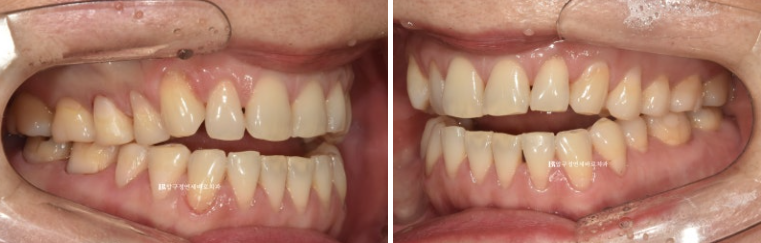

23.05~23.12

7개월에 걸쳐 1차세트 마무리 후 추가장치를 이해 리파인먼트 재제작에 들어갔습니다.

걱정하시는 교합도 잘 마무리 되었습니다.

추가장치의 목적은 미세하게 안 맞는 중심선을 맞추고 교정 후 어느정도 재발될 것을 예상해서 살짝 과개교합 상태를 만들어 놓는 것입니다.

아마 추가장치로 3개월 정도면 마무리 될 듯 합니다.

1차세트 7개월 소요되었고 추가장치 3개월이 걸린다면 총 치료기간은 10개월입니다.